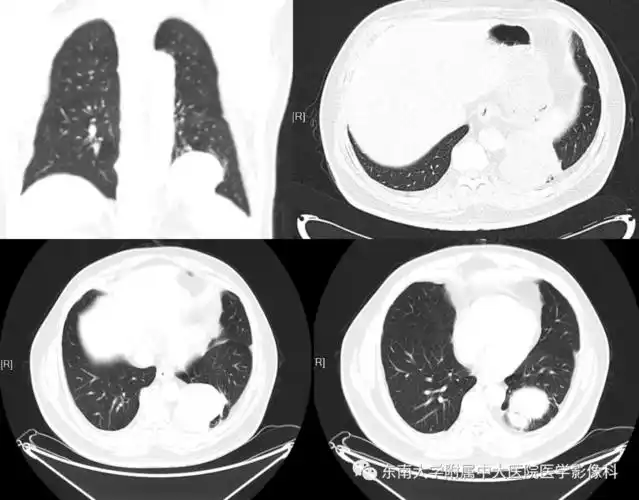

肺隔离症影像表现_郑孝飞